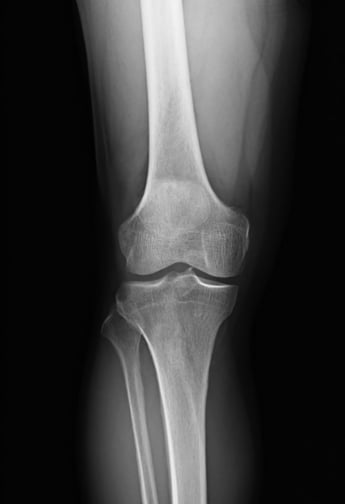

2400万人が悩む「変形性膝関節症」